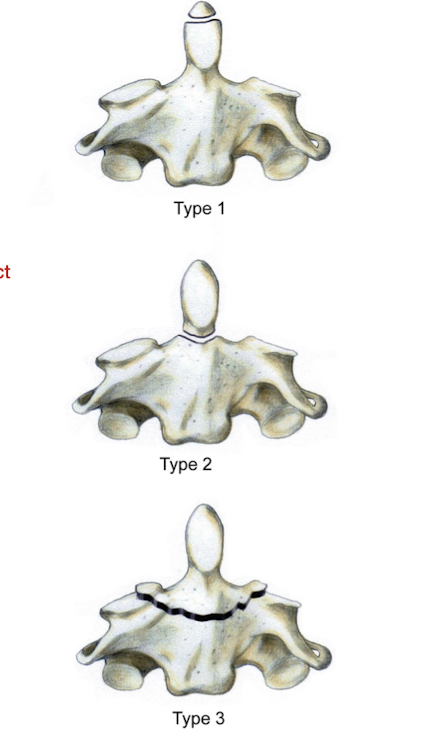

What are the 3 types of Odontoid Fractures?

Type 1:

Avulsion of the Hip

Type 2:

At junction of dens on the body of the axis

Type 3:

Below the junction of the dens

Fracture of the Axis: Dens

Which of the 3 types of Odontoid Fx is the most difficult to heal?

Why?

Type 2

Intact transverse and alar lig w poor bony contact